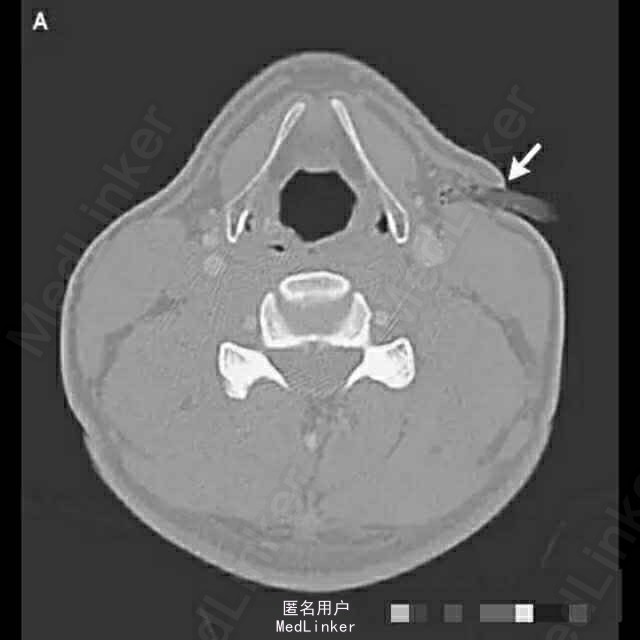

CT扫描可见颈部左侧、甲状软骨上方的软组织处有一异物,该物体穿过颈阔肌并延伸至胸锁乳突肌前缘。树枝从皮肤刺入颈部的深度为1.6 cm,未有伤及血管或气管的证据。